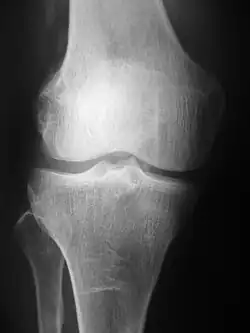

Projectional radiograph of the knee

Radiographs (originally called roentgenographs, named after the discoverer of X-rays, Wilhelm Conrad Röntgen) are produced by transmitting X-rays through a patient. The X-rays are projected through the body onto a detector; an image is formed based on which rays pass through (and are detected) versus those that are absorbed or scattered in the patient (and thus are not detected). Röntgen discovered X-rays on November 8, 1895,[5] and received the first Nobel Prize in Physics in 1901 for this discovery.[6] In film-screen radiography, an X-ray tube generates a beam of X-rays, which is aimed at the patient. The X-rays that pass through the patient are filtered through a device called a grid or X-ray filter, to reduce scatter, and strike an undeveloped film, which is held tightly to a screen of light-emitting phosphors in a light-tight cassette. The film is then developed chemically and an image appears on the film. Film-screen radiography is being replaced by phosphor plate radiography but more recently by digital radiography (DR) and the EOS imaging.[7] In the two latest systems, the X-rays strike sensors that converts the signals generated into digital information, which is transmitted and converted into an image displayed on a computer screen. In digital radiography the sensors shape a plate, but in the EOS system, which is a slot-scanning system, a linear sensor vertically scans the patient.

Plain radiography was one of the earliest imaging modalities used in clinical medicine and remained the most widely used for several decades. Due to its broad availability, speed, and relatively low cost, it continues to be a common first-line tool in radiologic evaluation. Despite advances in CT, MRI, and other imaging techniques, there are many conditions in which traditional radiographs remain helpful in diagnosis. These include arthritis, pneumonia, bone tumors, fractures, congenital skeletal anomalies, and certain types of kidney stones.